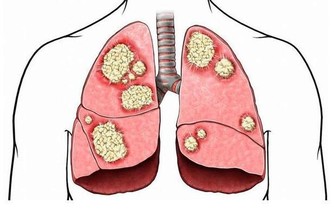

1 、幫你的關節“減負”

你肯定不知道你的關節每天在承受多大的力量,體重每增加1%,關節的承重就會增加4%,我們經常看到很多上了歲數的老年人,走起路來顫顫巍巍,腿都伸不直,可能就是因為在年輕時沒有好好愛護自己的關節,使得關節的使用壽命大大下降了。